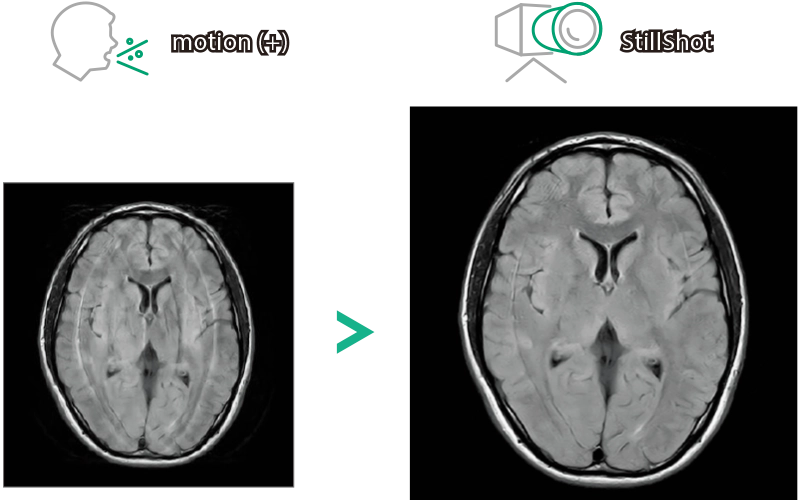

StillShot:The camera detects motion and suppresses the effects of body movement

FLAIR